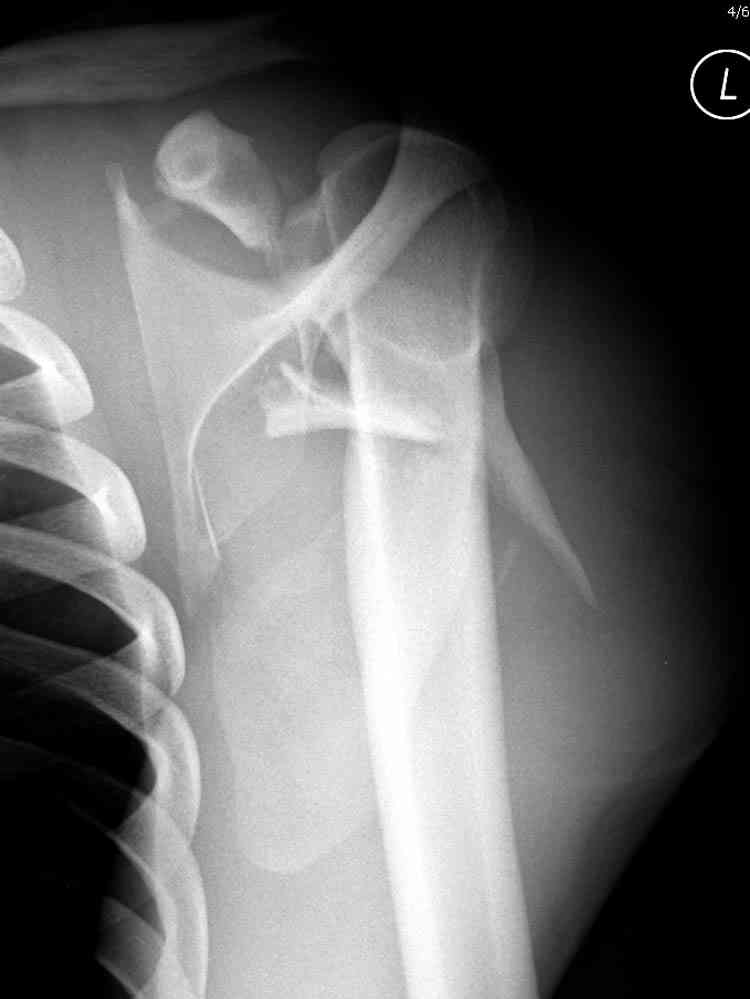

Re: Перелом угла лопатки

Никита, поздравляю с хорошей репозицией перелома

ключицы.

Если у вас имеется доказательство, что перелом лопатки изолированный, тогда нет необходимости операции, потому что стабильные изолированные переломы лопатки срастаются хорошо из-за хорошего кровоснабжения.

Для решения насчет оперативного вмещательства на лопатке сперва надо определиться с обьязательными ренгенологическими исследованиями, не менее трех стандартных проекций: прямая, аксиллярная и в позиции виде “Y”.

Прямую снимают под углом в 35 градусов от центра и вид “Y” в 90 градусов к нему. Несмотря на неудобства, больному необходимо сделать

аксиллярный снимок.

К-томографические и Трехмерные(3D)снимки крайне важны для определения внутрисуставных переломов и классификации.

Кроме анатомической классификации, переломы лопатки делятся на стабильные и нестабильные, внутри- и внесуставные и с вовлечением суставной поверхности.

Нестабильные внесуставные переломы лопатки типично сочетаются с переломами ключицы и ребер.

При отсутствии соединения верхнего пояса с телом из-за перелома ключицы и шейки лопатки имеется состояние "floating shoulder", как в аналогии повреждения около коленного сустава "floating knee" при переломах костей выше и ниже коленного сустава.